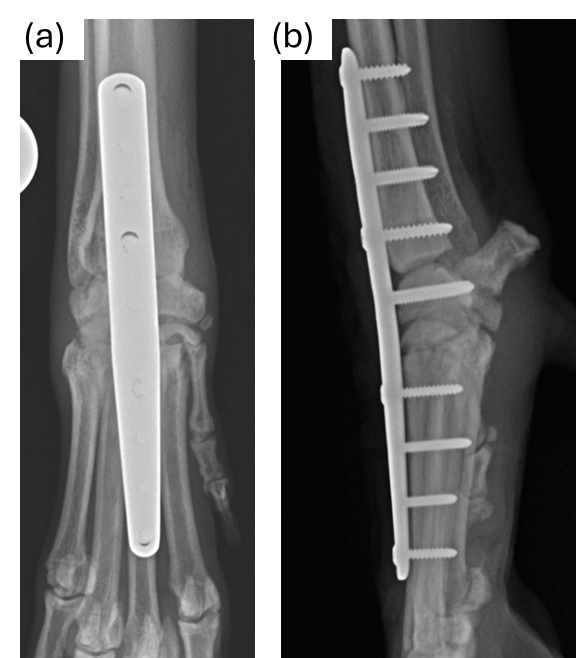

Alternatively, surgery is usually the most recommended management option and involves a salvage procedure of the affected carpus named ‘arthrodesis’, which means ‘joint fusion’, and it can be partial (only some of the joint fused) or complete (the whole joint is fused). The articular cartilage is burred away, bone graft is applied to the joint gaps and the wrist joint is bridged with an anatomic-specific bone plate and screws to provide stability (Figure 2) until the gaps are filled with new bone. Whilst the wrist joint is no longer functional, dogs adapt very well to this change by altering the way they use the limb (i.e. more elbow flexion, shoulder circumduction) and the clinical outcome is usually very good. However, arthrodesis is a particularly technical and demanding surgical procedure and complications may develop that could lead to a less optimal outcome. Therefore, a careful assessment by an orthopaedic specialist is recommended to allow the right decision-making regarding the appropriate management options.

Figure 2: Radiographic images of Anatomic-specific bone plate and screws, (a) Top view and (b) side view.